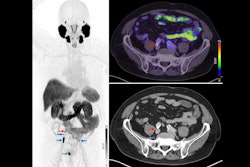

Given the high sensitivity and specificity of PSMA-PET for detecting prostate cancer, the researchers hypothesized that it could improve survival outcomes for patients if used prior to SRT compared to SRT without PSMA-PET guidance.

The study randomized 128 patients with biochemical recurrence after surgery to receive either standard-of-care SRT (n = 64) or PSMA PET-guided SRT (n = 64). Most patients in each group also received androgen deprivation therapy. The primary end point was failure-free survival (FFS), defined as the first occurrence of biochemical progression (PSA > 0.2 ng/mL), clinical progression, initiation of next-line therapy, or death.

The median PSA at enrollment for patients was 0.3 (0.1-3) ng/mL. Out of the 64 patients in the experimental arm, 33 (52%) had positive PSMA-PET scans and received intensified SRT. At a median follow-up of 37 months, these patients had an improved FFS (hazard ratio [HR], 0.5; p = 0.04) compared with the control group, according to the results.